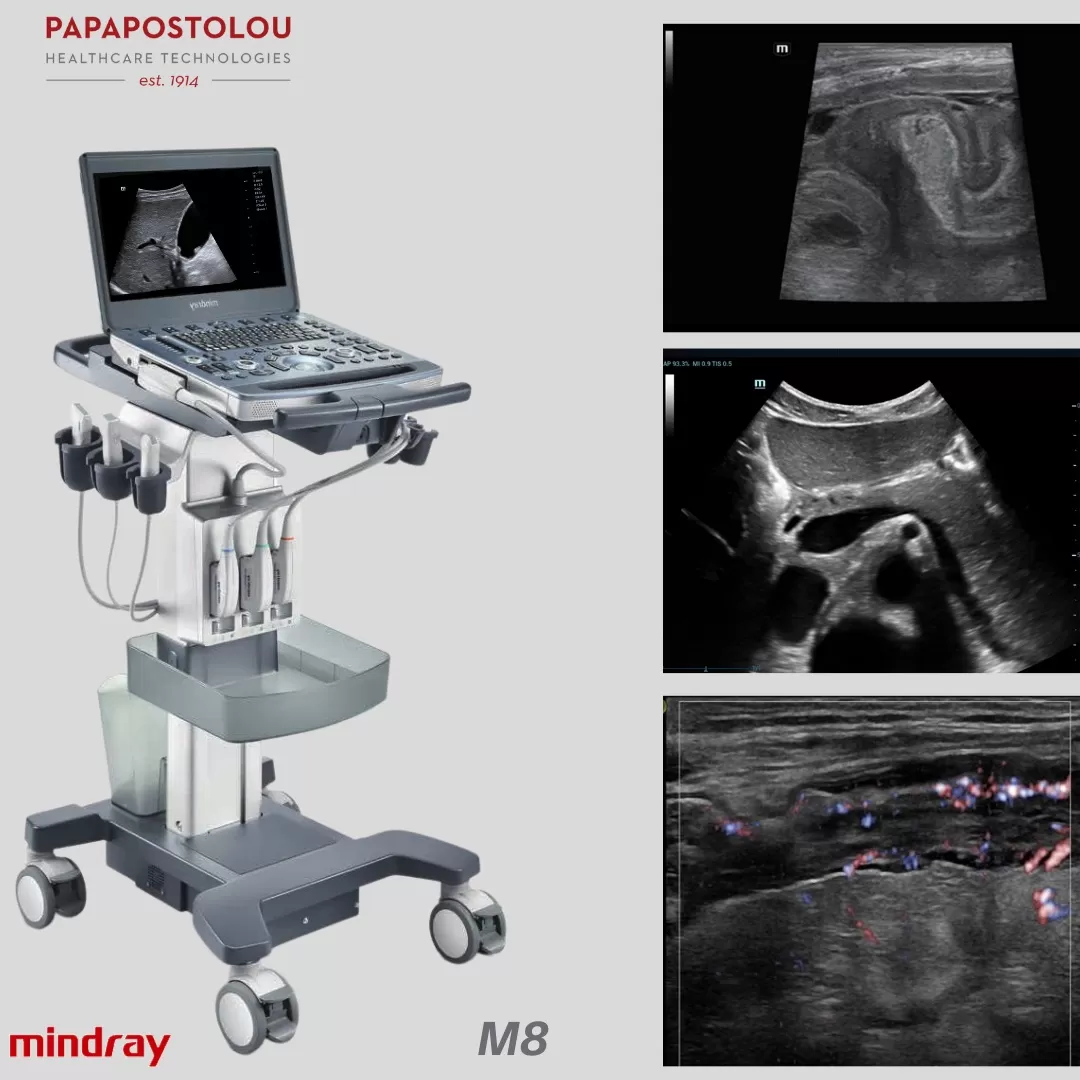

➡️ Τις πρωτοποριακές δυνατότητες των υπερήχων Μ6Τ & Μ8 της MINDRAY. Η υπερηχογραφία στην γαστρεντερολογία παίζει σημαντικό ρόλο στην εκτίμηση των παθήσεων της χοληδόχου κύστεως, χοληφόρων αγγείων, ήπατος, παγκρέατος και των εντερικών ελίκων, με σκοπό την ανεύρεση κυρίως φλεγμονωδών εξεργασιών, συγγενών ανωμαλιών του εντερικού σωλήνα (ανωμαλίες στροφής και καθήλωσης του εντέρου – malrotation, κύστεις εντερικού διπλασιασμού) καθώς και τον αποκλεισμό χωροκατακτητικών εξεργασιών.